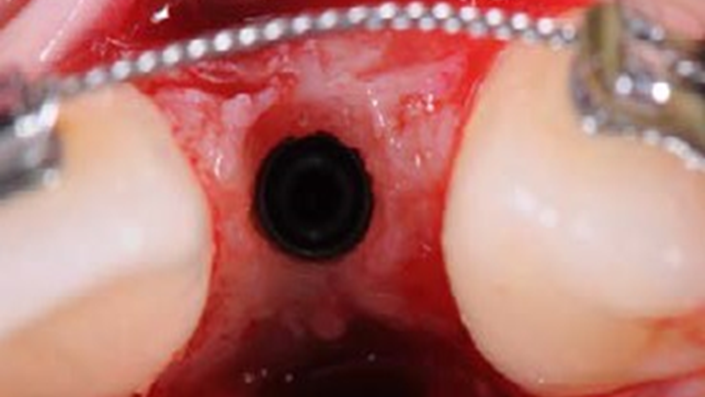

Clinical case: BPET PREDICTABILITY - State-of-the-Art SOCKET SHIELD

- Courtesy of Dr. Howard Gluckman, South Africa -

“AnyRidge is perfect for the anterior esthetic zone due to its strong initial stability & fast osseointegration.

Plus, KnifeThread® ensures space maintenance when using the PET/Socket Shield/Root Membrane Technique, showing excellent bone growth.”